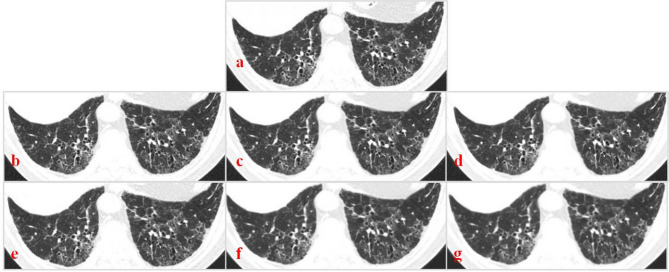

Methods: This study prospectively enrolled 21 patients with early-stage ILD. All patients underwent high-resolution CT (HRCT) and low-dose CT (LDCT) scans. HRCT images were reconstructed with HIR using standard settings, and LDCT images were reconstructed with DLR (lung/bone kernel) in a mild, standard, or strong setting. Overall image quality, image noise, streak artifacts, and visualization of normal and abnormal ILD features were analysed.

Results: The effective dose of LDCT was 1.22 ± 0.09 mSv, 63.7% less than the HRCT dose. The objective noise of the LDCT DLR images was 35.9-112.6% that of the HRCT HIR images. The LDCT DLR was comparable to the HRCT HIR in terms of overall image quality. LDCT DLR (bone, strong) visualization of bronchiectasis and/or bronchiolectasis was significantly weaker than that of HRCT HIR (p = 0.046). The LDCT DLR (all settings) did not significantly differ from the HRCT HIR in the evaluation of other abnormal features, including ground glass opacities (GGOs), architectural distortion, reticulation and honeycombing.